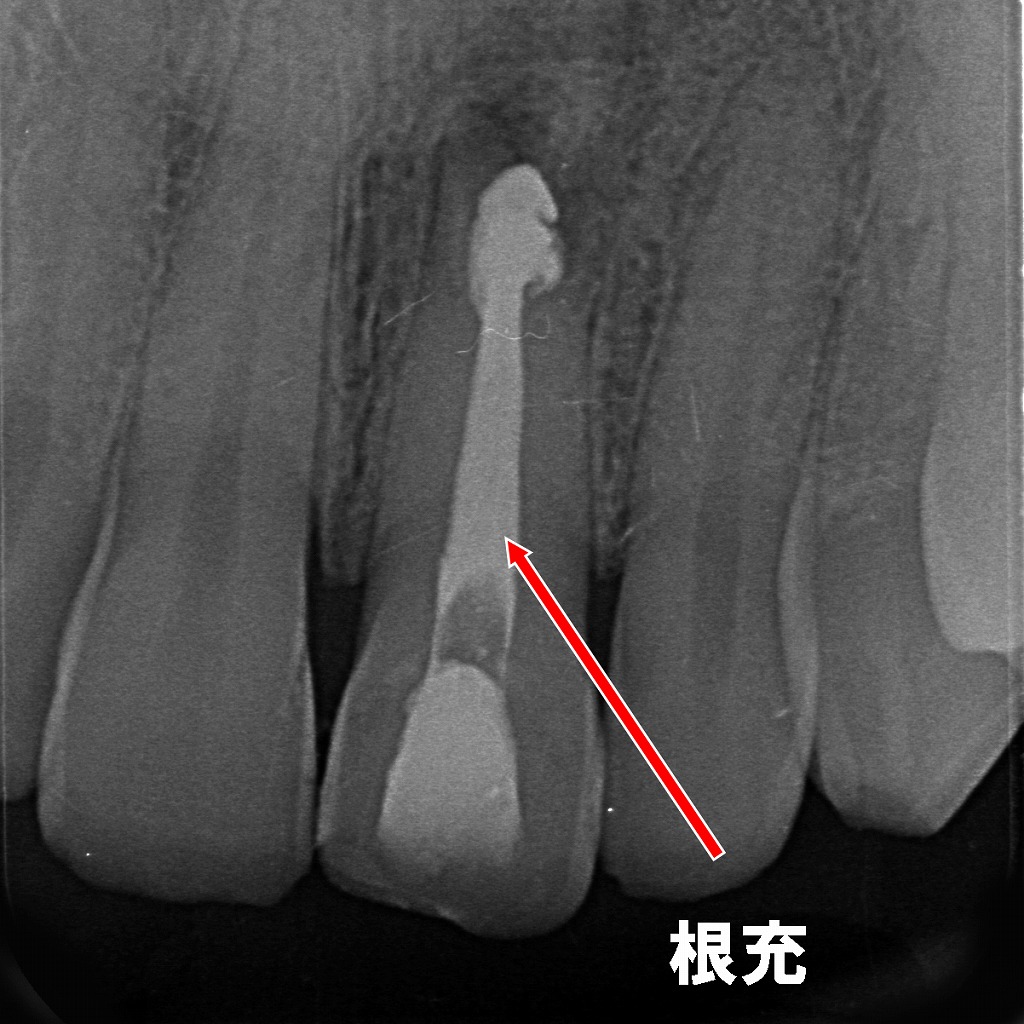

📌 画像の解説:病的歯根吸収に対する根管治療

① 1枚目:ファイル挿入による根管長測定

内容のポイント

- 根管内にリーマー(ファイル)が挿入され、根管の長さ(作業長)を測定している状態。

- 矢印上部では、病的歯根吸収により歯根外側が不規則に溶けた透過像が確認できる。

- 外部吸収がある症例では、根尖形態が不明瞭になりやすく、適切な作業長決定が特に重要。

② 2枚目:根充後の状態(治療完了時)

- 根管内がガッタパーチャでしっかり根充された状態。

- 吸収部位(矢印)は根尖周囲に透過像として残るが、

→ 感染源の除去が適切に行われ、内部から封鎖されていることが確認できる。 - 吸収歯の根管治療としては良好なシールが得られている像。